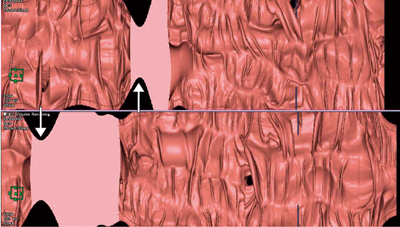

従来より,AZE VirtualPlace 雷神の大腸解析ソフトウェアにも,「展開像(opened image)」として標準搭載されている。最新版では腸管径による補正を施した展開像を選択可能で,腸管の大腸襞や構造物などの歪みが少なく補正された画像を表示可能となっている。腸管拡張の程度に合わせて,腸管径が長い領域は広く,短い領域は狭く展開するため,腫瘍などによる狭窄部は狭窄として明確に認識可能である(図1)。

CTCの診断に際しては,まず病変候補の絞り込みを行う。体位変換にて移動しているかどうかを確認することで,残便・残液などの偽病変の多くを簡便に鑑別可能であるものの,2D画像や仮想内視鏡画像のみでは,両体位で同一のものが同一の場所にあることを確認するのは意外と難しい。展開像を用いることで,周囲の正常構造と比較しての相対位置を確認することで,比較的容易に鑑別可能となる(図2)。

図2 展開像(opened image)

下行結腸の早期大腸がん(0-Ⅱa+Ⅱc,12mm大)。半月ひだ上の結節状隆起として描出されている(○印)。両体位ともに同じ半月ひだ上に結節状隆起があるため,病変の可能性が高いと判断できる。この画像のみで表面の形態を判断するのは困難であるが,ほかの腸管粘膜面と比較して,同部が限局性に隆起していることが容易に検出可能である。